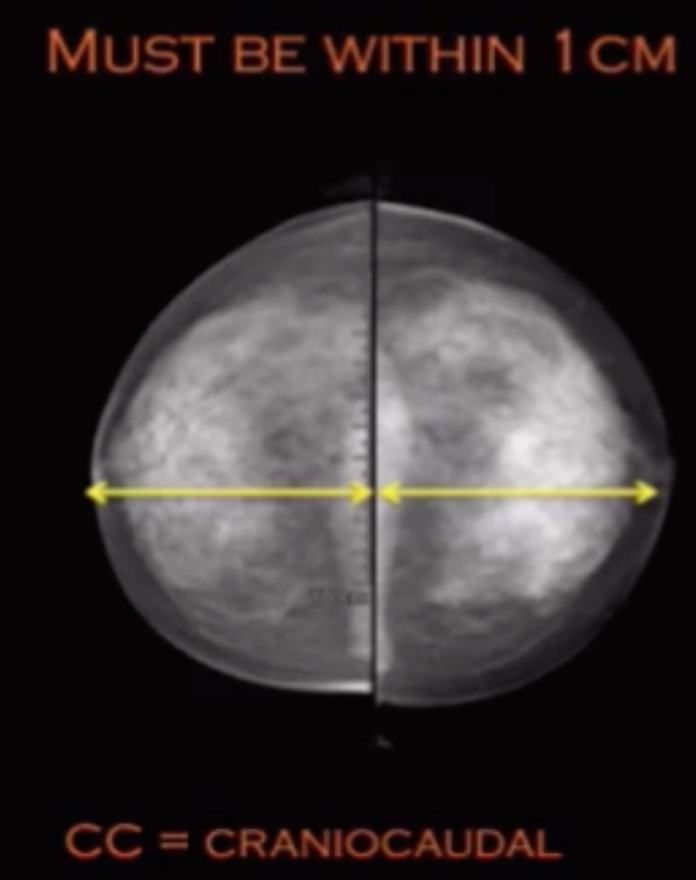

• Draw line from nipple to border of pectus muscle = posterior muscle line

• This line needs to be within 1 cm of a line drawn from nipple posteriorly on the CC view

Craniocaudal (CC)

• Patient faces machine

• Images posterior and superior breast very well

• Compressed in the axial plane